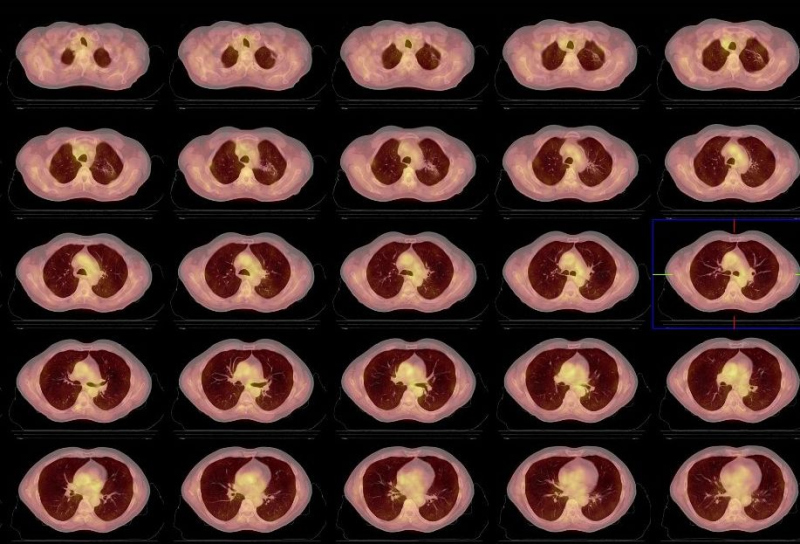

Se indica estudio PET de cuerpo entero y PET-CT torácico para investigar los hallazgos previos. Tanto en el primero (fig. 1) como en el PET-CT torácico (figs. 2, 3 y 4), se detecta acúmulo patológico de la FDG en lóbulo pulmonar superior izquierdo (2 cm, SUVmax=4,2) que se interpreta como un implante nodular maligno. En mediastino se comprueba captación patológica de la FDG en región perihiliar izquierda (2,5 cm, SUVmax=4,1) que corresponde probablemente a una adenopatía mediastínica maligna.